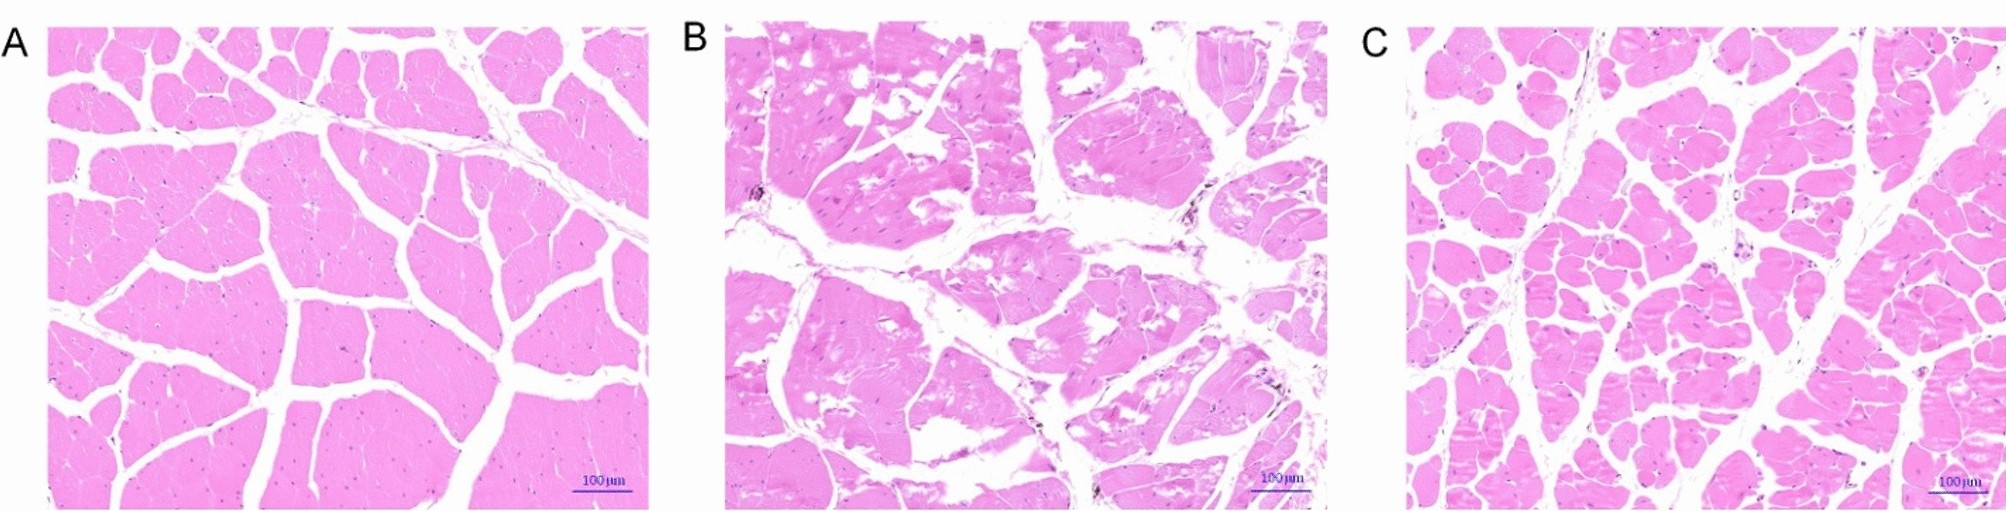

Histopathological observation of Chinese soft-shelled turtles infected with furunculosis pathogens. A was normal control group (NC), B was infection group (Lb18), C was infection treated with NAC group (Lb18 + NAC).